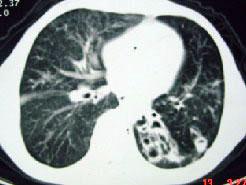

男,12岁,反复咳嗽咳痰多年,CT如图3,最可能的诊断为 ( )A.先天性支气管囊肿B.肺结核C.肺发育不全D.肺隔离症E.肺脓肿

问题 男,12岁,反复咳嗽咳痰多年,CT如图3,最可能的诊断为 ( )

选项 A.先天性支气管囊肿 B.肺结核 C.肺发育不全 D.肺隔离症 E.肺脓肿

答案 A